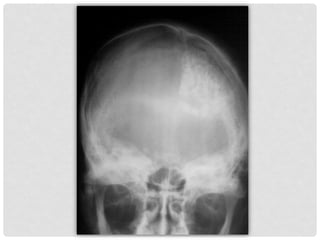

Hallazgo radiológico en

proyecciones simples de

cráneo, AP y lateral, en

paciente masculino de 22

años con cefalea, sin mas datos

clínicos en su solicitud médica.

PROYECCIONES

RADIOLÓGICAS

SIMPLE,

INICIALES.

Las radiografías simple de cráneo

muestran calcificaciones

intracraneanas con patrón

giriforme, proyectadas en

topografía del hemisferio cerebral

izquierdo.